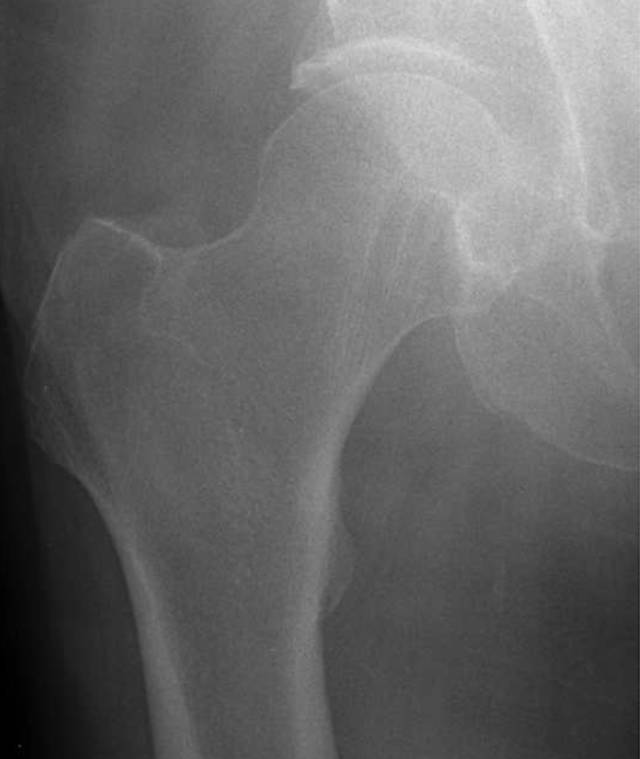

即使正确定位和技术上优秀的射线照片,一些骨折在X线片上是不可检测的,因为它们是无位移的。这些骨折有症状,并有相应的临床表现和受伤的机制,但他们没有明显的X光片。在本质上,X射线照片结果是假阴性的,因为该方法本身局限性不足以显示断裂。 射线照片上的急性骨折的检测通常需要它们在一定程度上移位。由于临床体征高度怀疑,通常需要进一步评估额外的成像,特别是如果这种成像的结果将影响临床管理。这样的例子有上了年纪的人或老年人在地面踉跄之后加上不能承受体重,髋部疼痛, 骨质疏松通常进一步增加了检测不位移性骨折的难度。放射线检查结果可能是阴性或模棱两可的,因为骨矿物的弥漫性损失使不位移性骨折线不太明显。因为近端股骨骨折的管理通常是手术,当根据临床表现的骨折的预测概率高时,通常进行进一步的CT或MRI评估。美国放射学会[12]建议对中年或老年患者进行MRI(等级9)CT(等级6)或放射性核素骨扫描(等级4),这些患者在放射照片显示阴性或不确定性,用CT与MRI的诊断优势以排除存在放射学上隐匿性髋骨骨折[13]。如果MRI不可用或者患者对MRI具有禁忌症,CT可以提供最佳选择。然而,MRI在检测骨髓水肿方面优越(图3)。骨扫描已应用于放射摄影术的初步诊断[14],但在我们的实践中最少使用,因为CT更为普遍。床旁超声检查最近被研究作为一种检测第五跖骨骨折的方法,基本上作为身体检查的延伸,并且与放射线照片相比显示出一些前景[15]。然而,在多发伤筛查情况下,超声检查的成像效果不如放射照相[16]。

图3A-65岁的男子在地面摔倒后,在射线照片上没有看到移位性骨折。

A,前后放射照片显示正常。侧视图也是正常的。患者抱怨右髋疼痛,无法承受体重或步行。